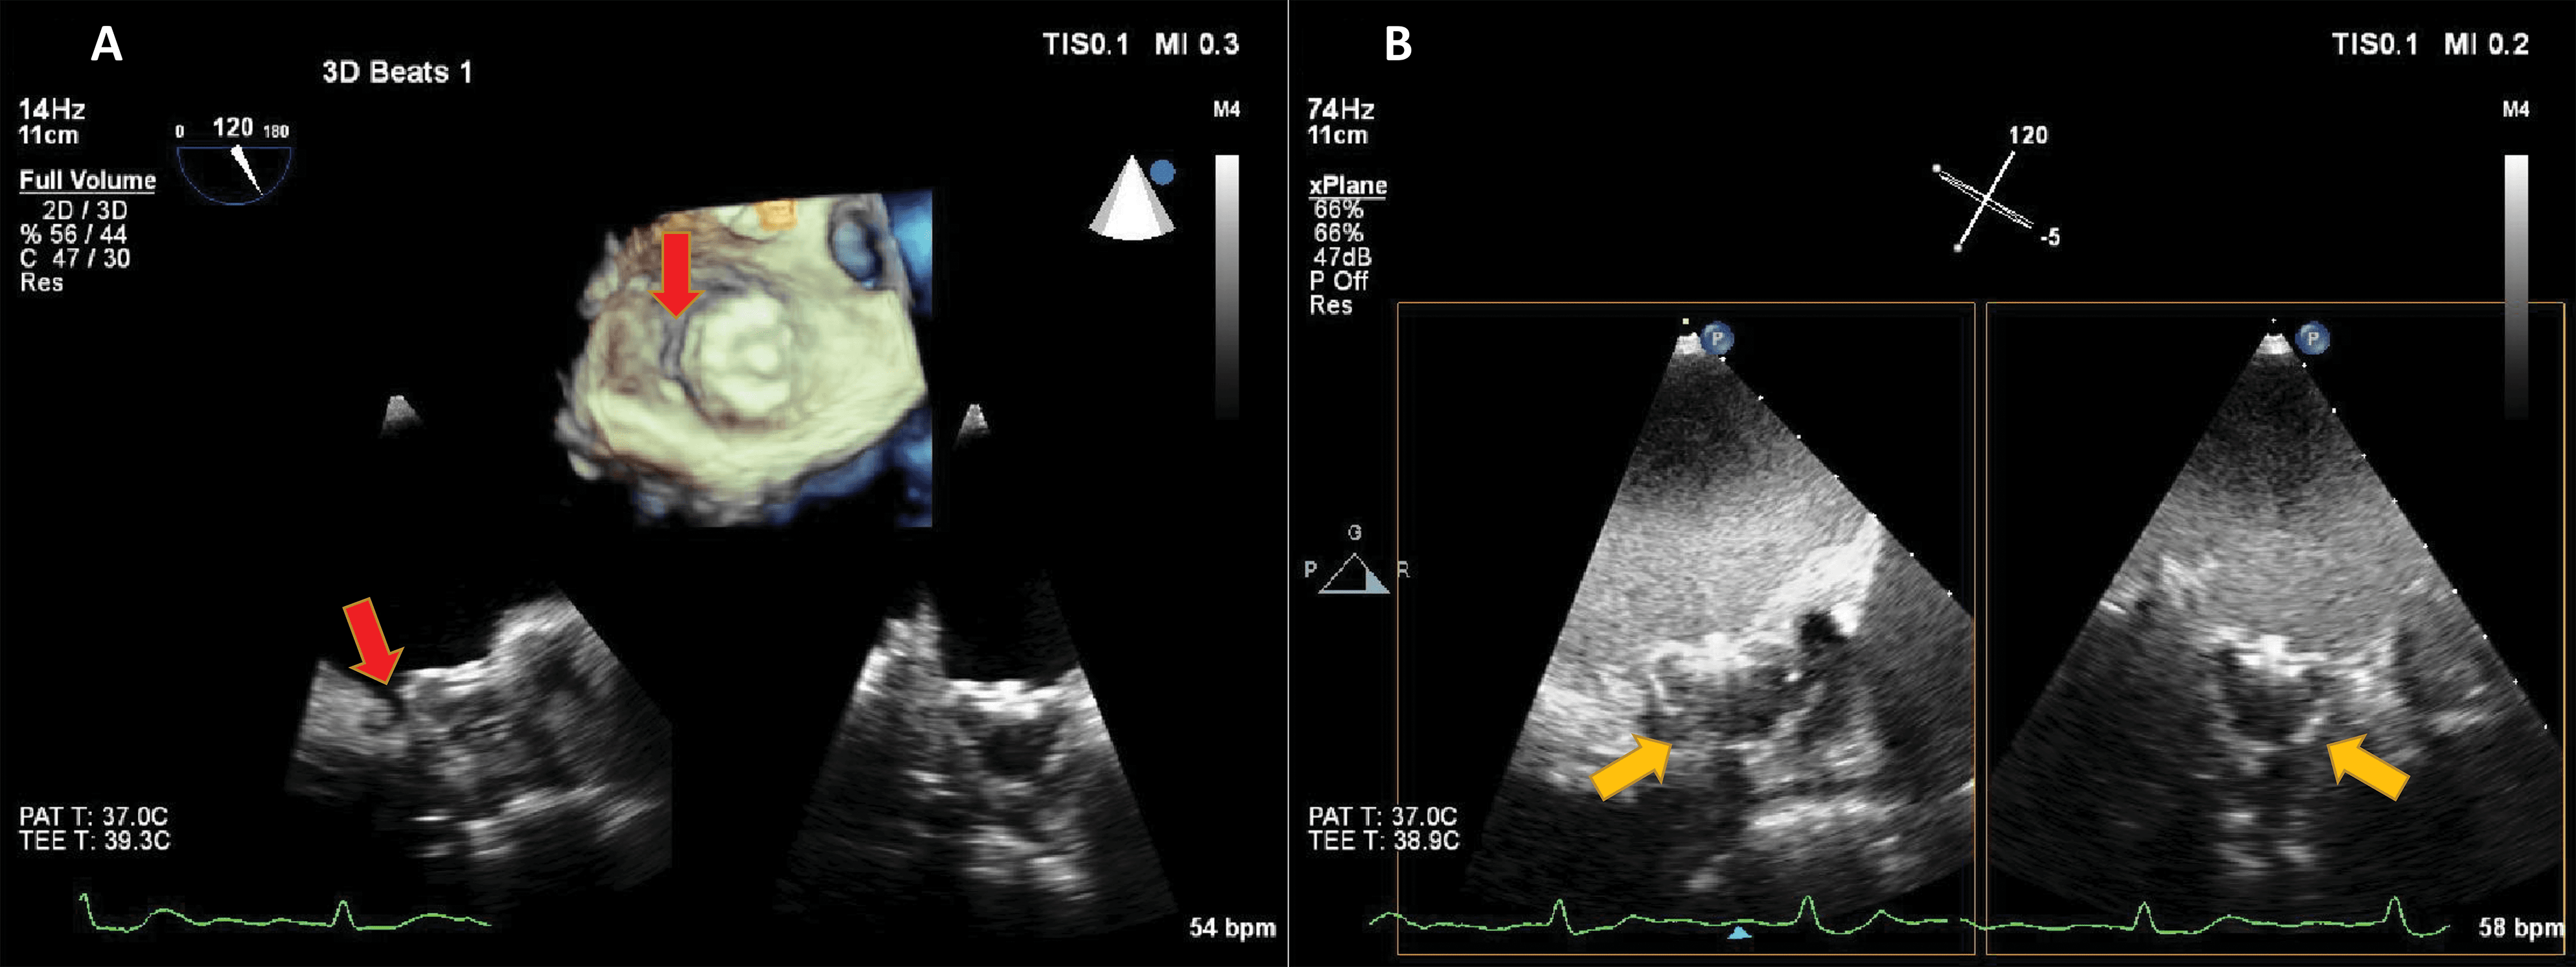

UEA have largely been used in the detection of LV thrombi [76, 77, 78]. This is in fact an application of the LVO method, enhancing the delineation between the wall, cavity and the thrombus mass (Fig. 10, Ref. [79]). However, prognostic implications for small mural thrombi are not clear. Myocardial perfusion detection, as described above, may help to diagnose small intracardiac or even intramural masses, by the presence and the dynamics of the vascularization inside the mass [80]. By adding a quantitative approach, it may even be possible to differentiate not only thrombi from tumors, but also benign from malignant tumors [79] (Fig. 11, Ref. [79]).

Fig. 11.Hyperechoic and hypermobile mass in a normal LV. The image quality is good, and the mass is hyperechoic. (A) 4-chambers view. (B) 2-chambers view. (C) Signal intensity quantification after a flash-replenishment cycle. The replenishment of the mass is similar to the interventricular septum, but with higher intensity, signalling the presence of a capillary vascularisation, with a higher density than the myocardium. (D,E) Parametric map of signal intensity, demonstrating the same features of the mass. In this patient the mass was finally diagnosed as a hypervascular metastasis from a lung carcinoma. Images modified with permission from Strachinaru et al. [79].